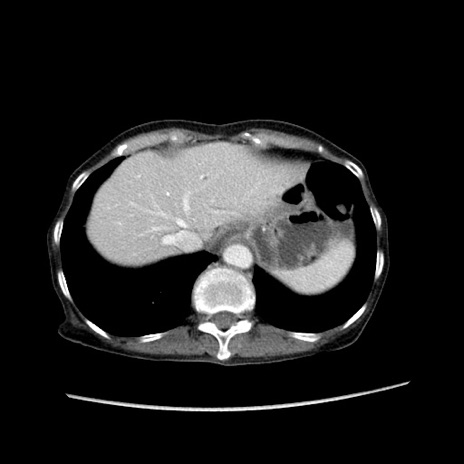

症例25(横断像)

【症例】80歳代女性

【主訴】胸のつかえ感

【現病歴】約9時間前に食後から胸のつかえた感じあり、嘔吐あり、来院。

【既往歴】胃癌(全摘)、胆摘、虫垂炎

【身体所見】心窩部に圧痛あり、反跳痛なし。

【データ】WBC 5700、CRP 0.05